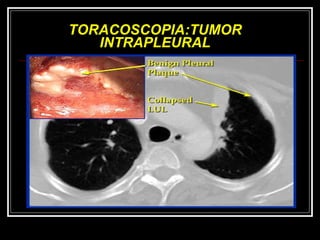

TORACOSCOPIA:TUMOR INTRAPLEURAL